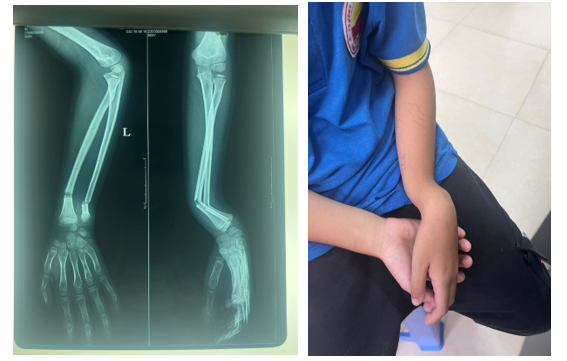

Ngoài ra, còn có các dấu hiệu tổn thương thần kinh ít gặp như liệt vận động do mất khả năng duỗi khớp cổ tay, bàn tay và các ngón tay. Để xác định chính xác về vị trí, đường gãy hoặc hướng di lệch của vết thương, bác sĩ sẽ tiến hành chụp X – quang trên hai bình diện thẳng và nghiêng. Trong một số trường hợp, cần chụp CT hoặc MRI bổ sung để đánh giá phạm vi ảnh hưởng của vết gãy. Điều này giúp bác sĩ đưa ra chẩn đoán chính xác và điều trị phù hợp cho từng trường hợp.

Chụp X – quang hoặc MRI sẽ giúp bác sĩ xác định vị trí, phạm vi và mức độ nghiêm trọng của vết nứt. Một số phương pháp phẫu thuật có thể áp dụng bao gồm: